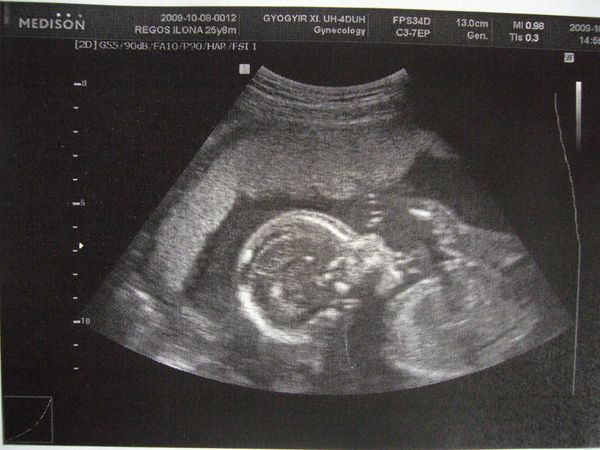

Aki pedig mostanában megy UH-ra annak drukkolok, hogy minden rendben legyen és esetleg a neme is kiderüljön

Tőlem ma reggel levették a vért az AFP-hez, holnap délre kész az eredmény, aminek nagyon örülök, mert a nőgyógyászhoz hétfőnként lehet menni, így nem kell várnom plusz egy hetet, pár nap és mehetünk kukucskálni

Már nagyon várom, remélem, minden OK odabent. És ha magamutogatós a kicsike, talán az is kiderül, mije van a lába között, de ha nem, az sem baj